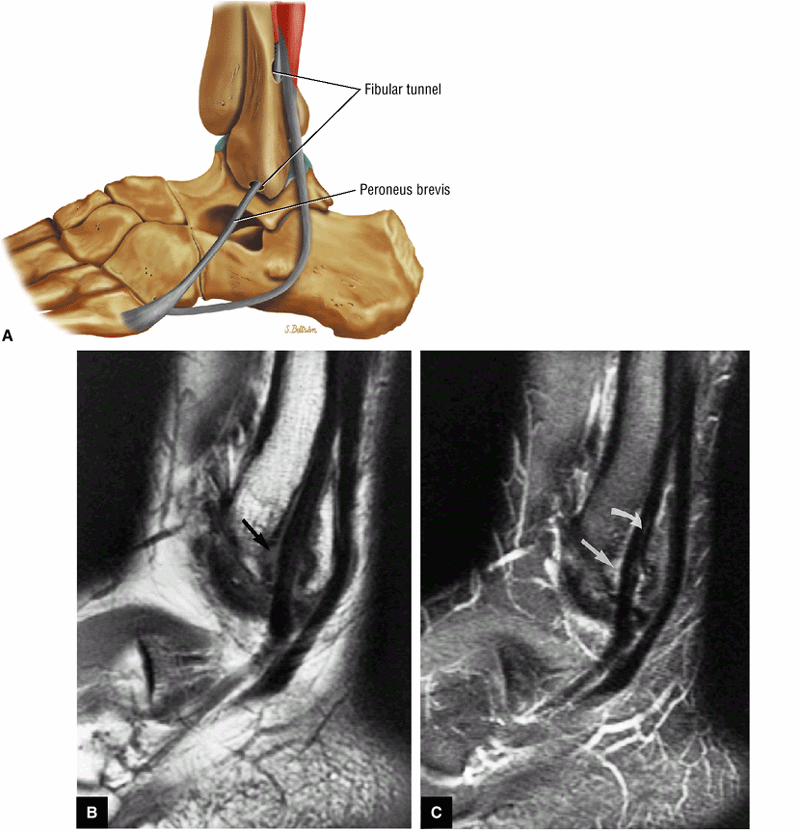

|

![]() |